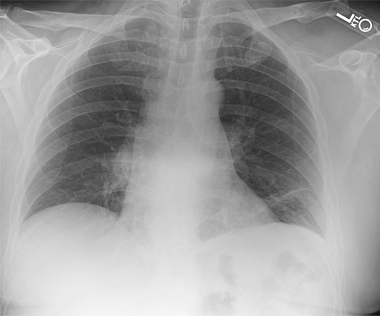

AP chest radiography should be performed as part of initial trauma series. On a nonrotated chest radiograph, assessment of lateral scapular displacement can be performed by measuring distance between a midline thoracic spinous process and the medial borders of the scapula on both the injured and uninjured sides. A difference > 1 cm is diagnostic of scapulothoracic dissociation [1, 5]. Orthogonal radiographs of any suspected upper extremity fracture or dislocation should also be obtained. Immediate Vascular imaging with CT angiography is recommended in patients with suspected scapulothoracic dissociation [2]. CT myelography, MRI, or EMG studies can be used for evaluation of brachial plexus injuries. Nerve studies are usually reserved for at least 3 weeks after injury to assess degree of recovery, if any.